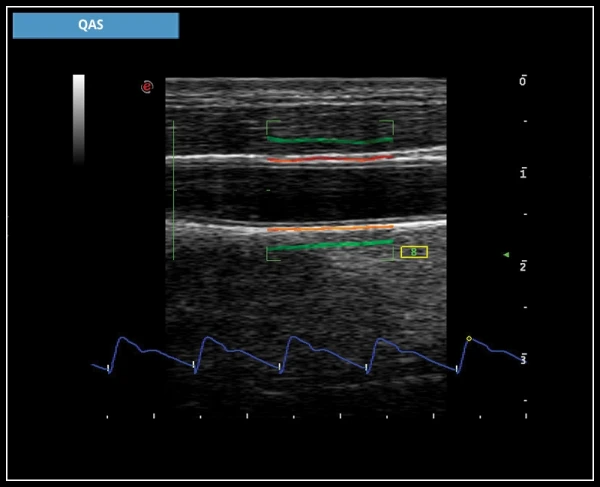

QIMT: Автоматическое определение толщины интима-медиа в реальном масштабе времени, включая стандартное отклонение и индекс надежности, на основе анализа радиочастотного сигнала.

QAS: Технология анализа радиочастотных данных позволяет автоматически и точно измерять прочность стенки сонной артерии, а также автоматически вычислять индексы PWV, CC, AI, α, β.